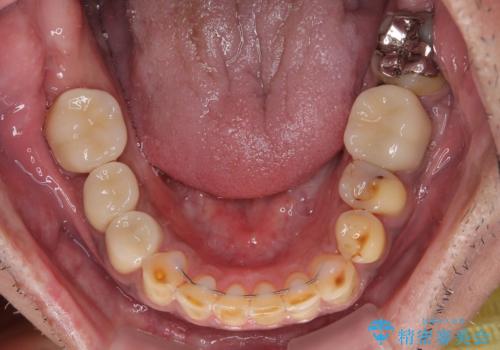

矯正治療は想定通り長期化しましたが、しっかりと奥歯の咬み合わせを向上させて前歯の被蓋を改善させることができました。

目立つ銀歯やすり減った前歯がセラミッククラウンとなり、患者様には大変満足していただけました。